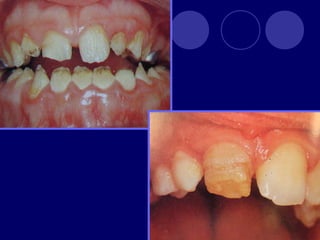

DENTINOGENESIS IMPERFECTA TIPO I:asociada a padecimiento esquelético, asociada a osteogénesis imperfecta (escleróticas azules, sordera, múltiples fracturas,etc.)  Dos denticiones  Dientes blandos, consistencia terrosa  Rx: cámaras pulpares obliteradas

TIPO II:  Dientesde color: amarillo, pardo azulado u opalescente con brillo translúcido, raíces color ámbar  Rx: coronas bulbosas, cámaras pequeñas o ausentes, raíces delgadas y cortas TIPO III: (SHIELDS)  Temporal: translúcido, ámbar  Permanente: normal